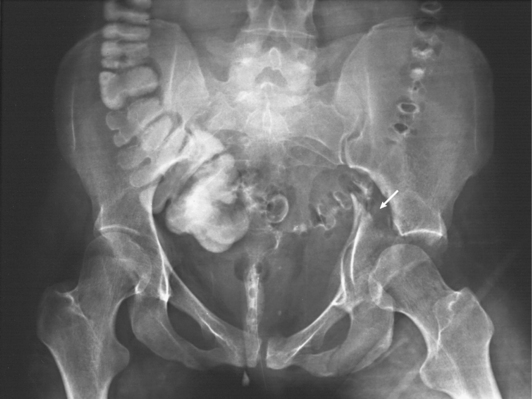

Structures shown: This projection shows the pelvis, including the following: both hip bones; the sacrum and coccyx; and the head, neck, trochanters, and proximal portion of the femora (Fig. 28-19).

For optimal imaging, a grid must be level, centered to the central ray, and correctly used at the recommended focal distance, or radius. When a grid is placed on an unstable surface such as the mattress of a bed, the weight of the patient can cause the grid to tilt “off-level.” If the grid tilts transversely while using a longitudinal grid, the central ray forms an angle across the long axis. Image density is lost as a result of grid “cutoff” (Fig. 28-3). If the grid tilts longitudinally, the central ray angles through the long axis. In this case, grid cutoff is avoided, but the image may be distorted or elongated.

Fig. 28-3 Mobile radiograph of proximal femur and hip, showing comminuted fracture of left acetabulum. A, Poor-quality radiograph resulted when grid was transversely tilted far enough to produce significant grid cutoff. B, Excellent-quality repeat radiograph on the same patient, performed with grid accurately positioned perpendicular to central ray.